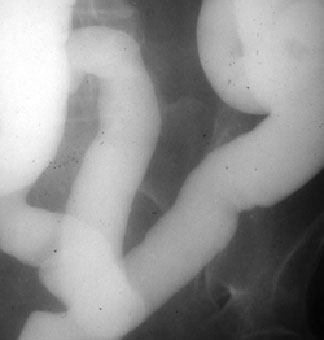

Recibe este nombre el aspecto de los pliegues intestinales engrosados, lisos, rectos y perpendiculares al eje longitudinal de la luz en el estudio del tránsito intestinal baritado. El signo se presenta cuando existe infiltración difusa de la submucosa por edema o hemorragia intramural (traumatismo, isquemia, toma de anticoagulantes, etc).

El aspecto de los pliegues en pila o columna de monedas es más evidente en el yeyuno que en el íleon, debido al mejor desarrollo y mayor tamaño de los pliegues yeyunales.

Por el aspecto de los pliegues intestinales, este signo también se ha denominado Signo de los pliegues en empalizada o en hilera de estacas.

Otro ejemplo de este signo.